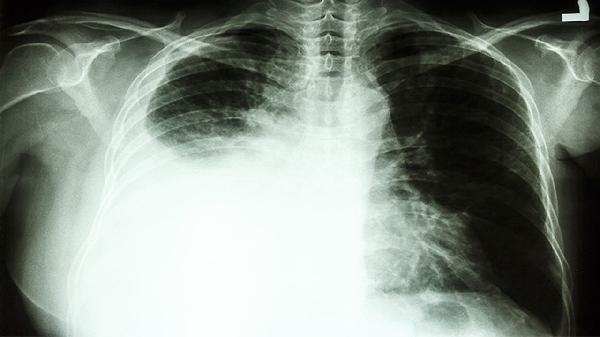

肺癌属于恶性肿瘤,治疗需根据病理类型、分期制定个体化方案。早期患者以手术根治为主,中晚期需结合放化疗、靶向治疗或免疫治疗。中药辅助治疗时,必须由肿瘤科与中医科医师联合评估,监测肝肾功能及药物不良反应。患者切勿自行用药或中断规范治疗,以免延误病情。